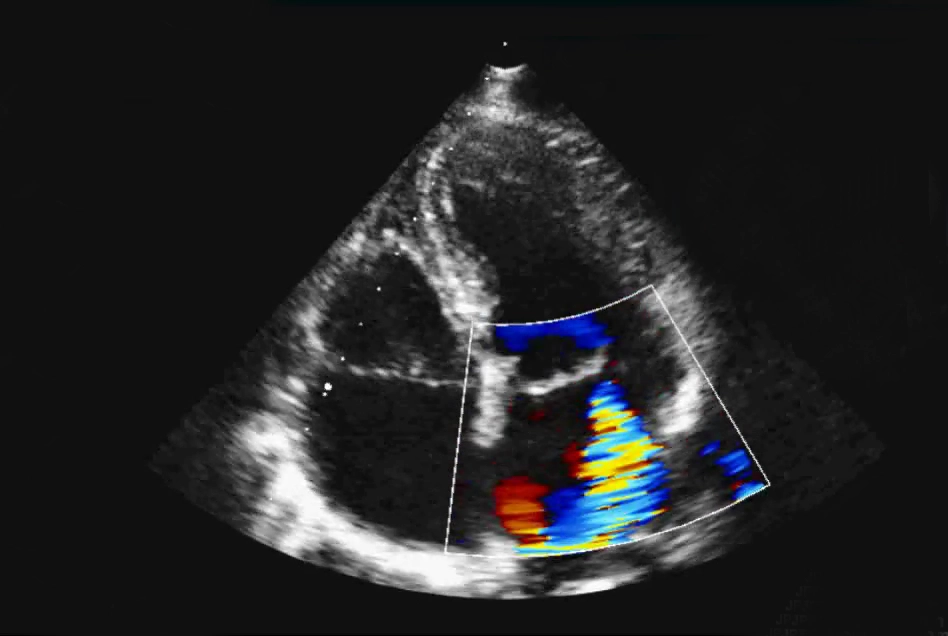

Ausführliche online Hands-On Videos für das Schallen der Grundschnitte und wichtiger Modalitäten (Farbdoppler, M-Mode, PW-Doppler, CW-Doppler) stehen Ihnen zusätzlich zur Verfügung, > 30 Videos, so können Sie Ihre praktischen Echo-Fähigkeiten verbessern

Zusätzlich können Sie in dieser Simulation zahlreiche Fallbeispiele von Pathologien selbst bearbeiten und das Befunden an virtuellen Patienten mit echten Echobildern erlernen. Sie lernen viele Problemstellungen kennen, die im Alltag sehr häufig vorkommen. Außerdem wird Ihnen die Vielzahl der interaktiv bearbeiteten Fälle die Arbeit im Klinik- und Praxisalltag nach dem Kurs deutlich erleichtern.